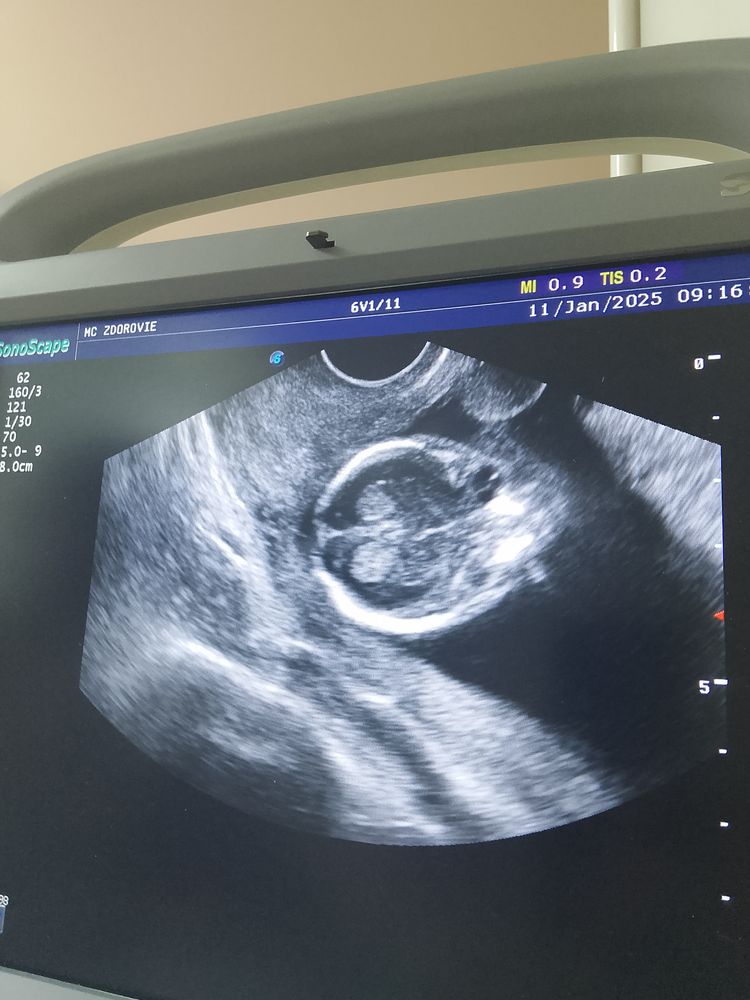

Что изображено на узи?

Вид сверху на голову,мозг и там немного глазик

Голова, мозг, глаза

Голова) вид сверху

Голова сверху и виден левый глаз

УЗИ 6+3 Для дневника. Узи 10 недель.